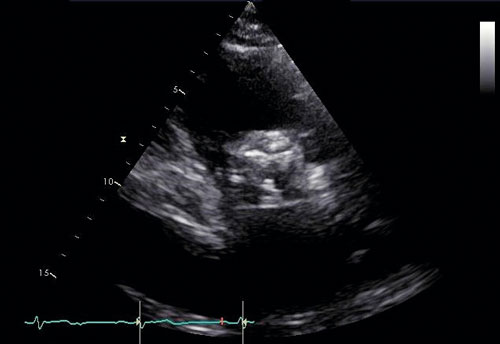

Ekokardiografi utgör en hörnsten i utredning av aortastenos (Figur 2, 3). Med kontinuerlig doppler kan tryckgradient samt medel- och maximal flödeshastighet beräknas, vilka tillsammans med uppmätt klaff­area ligger till grund för stadieindelning och prognos [10]. Utöver att visualisera klaffens grad av förkalkning ger undersökningen möjlighet att värdera övriga klaffars funktion, vänsterkammarens morfologi och funktion inklusive bestämning av ejektionsfraktion samt lungartärtryck. Transesofageal ekokardiografi kan i enstaka fall behövas för att ytterligare kartlägga anatomiska förhållanden inför exempelvis kateterburen intervention och för bättre bedömning vid samtidigt mitralisvitium [11]. Hjärtkateterisering används numera mycket sällan i diagnostiken och enbart när övriga metoder visat sig vara otillräckliga.

Figur 2. Ekokardiografi (parasternal kortaxelvy) visar ökad ekogenitet över tät aortastenos (trikuspid).